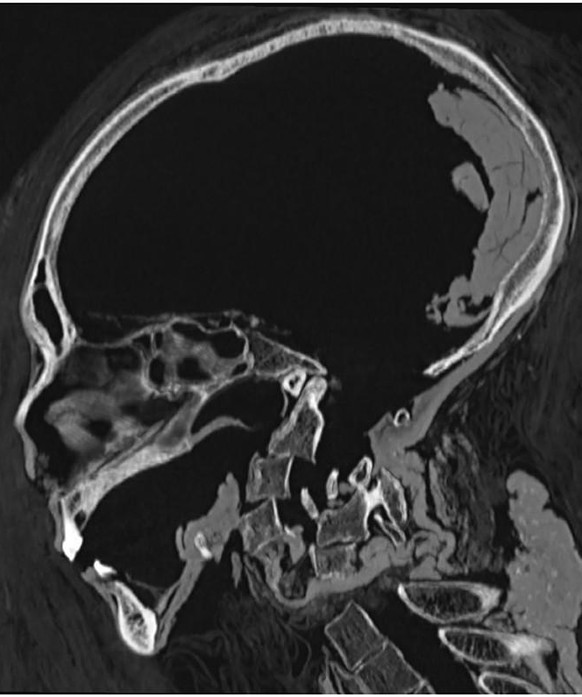

So auch der berühmte Ägyptologe Zahi Hawass. Er wollte einen «Einblick in das Aussehen, die Gesundheit, die Todesursache und die Art der Mumifizierung der Mumie von Pharao Amenophis I.» Grund genug für Hawass, den alten König in ein CT-Gerät zu verfrachten – und ihn digital zu entpacken. Denn der mumifizierte Körper Amenophis I. ist in der Neuzeit nicht entblösst worden, indem er aus seinem Mumienbinden-Kokon ausgewickelt wurde – ein Schicksal, das viele seiner Vor- und Nachfahren besonders im 19. Jahrhundert erleiden mussten.

Zum Zustand der Mumie entdeckten Hawass und Saleem überraschendes: Häufig wird berichtet, dass die alten Ägypter ihren Toten das Gehirn entfernten – und zwar durch die Nase oder ein Loch im Schädel. Die CT-Scans haben nun aber gezeigt, dass Amenophis' I. Gehirn intakt war. Ganz im Gegensatz zu den Mumien anderer Könige aus dem Neuen Reich, wie Tutanchamun oder Ramses II., denen das Gehirn entfernt wurde.

Die CT-Scans zeigen, wie bei der zweiten Bestattung mit einigen dieser Verstümmelungen umgegangen wurde: Unter anderem wurde der Kopf des Königs wieder auf den Halswirbeln fixiert sowie abgebrochene Finger im Bauchraum des Königs verstaut.

Der Scan des Schädels von Amenophis I. zeigt, dass der König, im Gegensatz zu vielen anderen königlichen Mumien, ein gutes Gebiss hatte.

Basierend auf der Schliessung der Epiphysenfuge der Röhrenknochen, der Schambeinfuge sowie aufgrund des Gebisses schlussfolgern die Autoren: «Das Todesalter Amenhotep I. liegt bei ungefähr 35 Jahren».